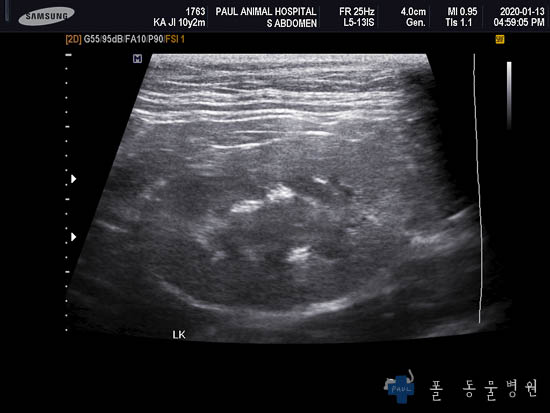

다음은 복부의 장기를 더 자세히 평가할 수 있는 초음파 검사 결과입니다.